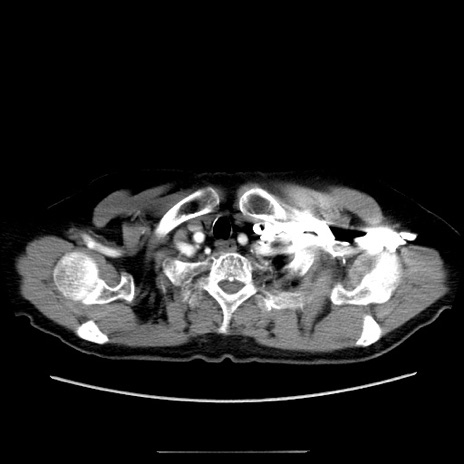

症例

冠状断像